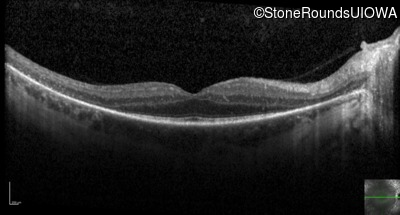

Optical Coherence Tomography - Left - 20/32 -2

Exemplar / OCT Stack

OCT Stack